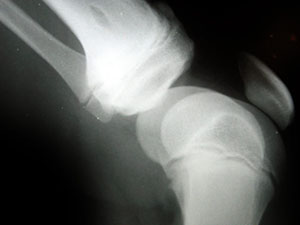

knee-arthritis-01Knee arthritis is a painful condition in which the joints in the knee become inflamed. Depending on the severity of the condition, it may limit an individual’s normal range of motion, forcing him or her to keep body weight off the affected knee. While there’s no known cure for arthritis of the knee, a recent study found herbal acupuncture to effectively treat the symptoms associated with this condition.